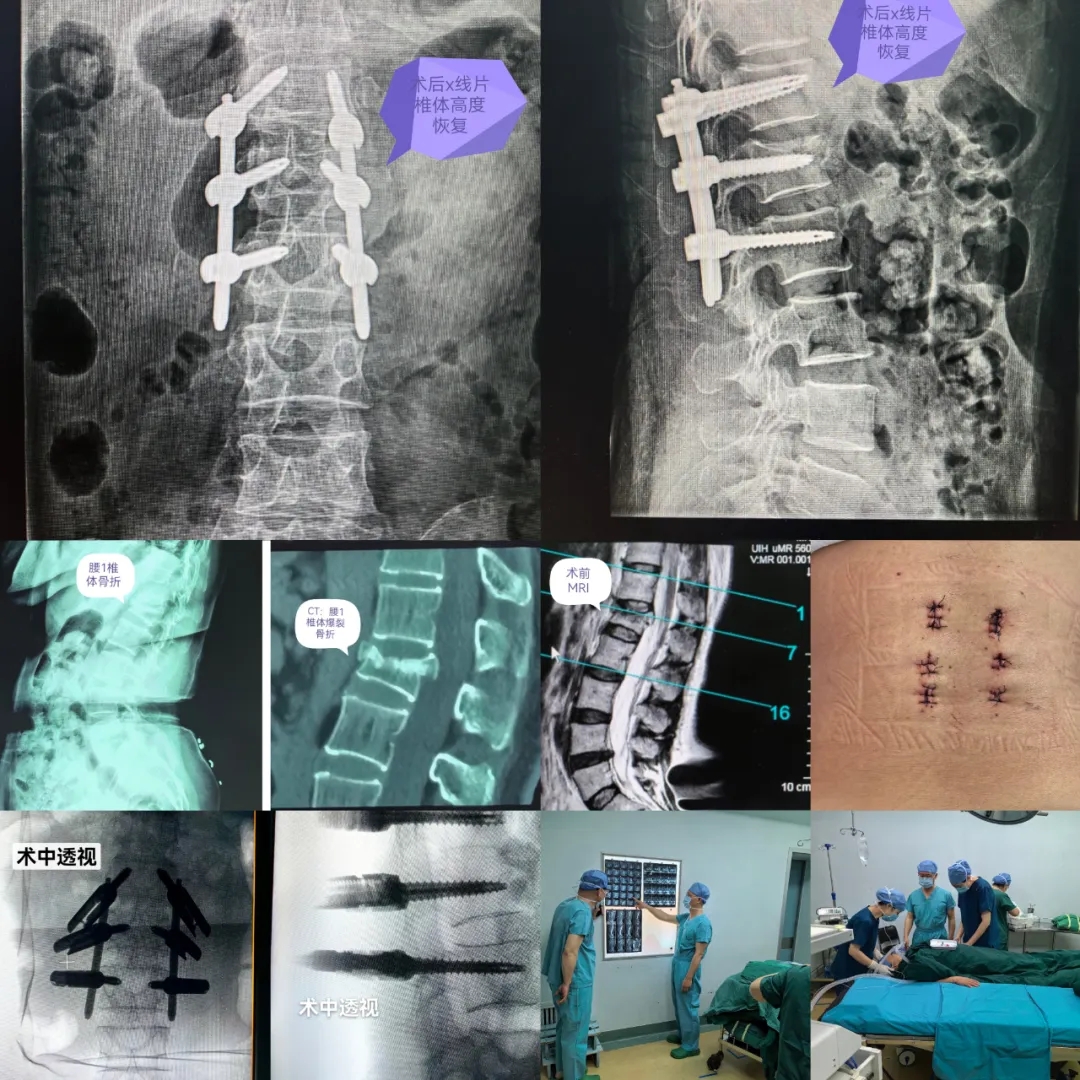

近日,山西省医院协会常务理事单位——太原市第二人民医院骨科为一位腰椎体爆裂骨折患者行微创经皮穿刺椎弓根螺钉经伤椎置钉内固定术。患者从手术到出院,仅三天时间。手术的成功意味着太原市第二人民医院骨科脊柱微创技术取得了新的突破和发展。

患者为女性,52岁,摔倒后腰背部疼痛、活动受限18小时入院,诊断为腰1椎体爆裂骨折。在医务科指导下,刘建国主任、贾士军主管医生和全科医务人员协同麻醉科、心内科、药剂科、中医科等兄弟科室开展多学科会诊,制定出详细手术方案。

经皮椎弓根螺钉内固定术是目前临床上应用比较广泛的椎弓根微创内固定技术,较传统开放椎弓根螺钉技术而言,具有创伤小、出血少、手术时间短、患者恢复快的优势。